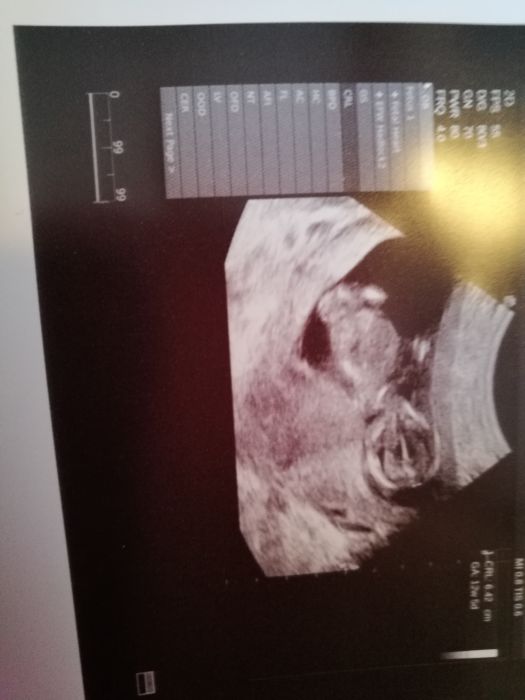

Ja teda taky na Fb nejsem... ja mam ted kontrolu az 28. 1. A pak hned 30.1. uz mam screening, tak na nej jsem mega zvedava. Dneska jsem 11+5